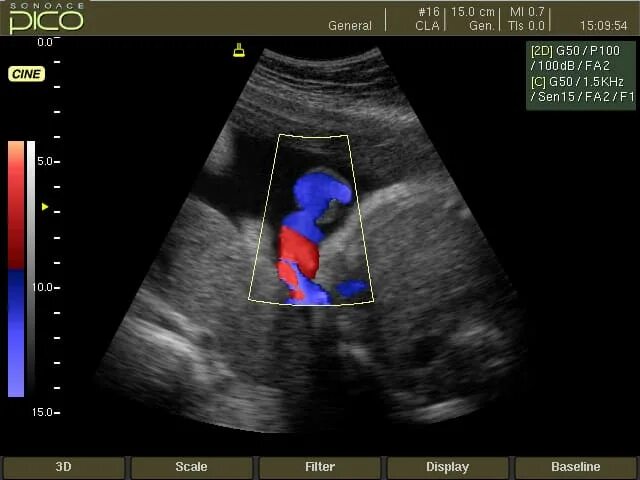

Допплер для беременных для чего